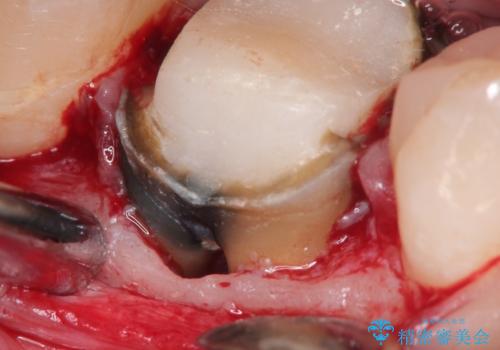

- 奥歯がズーンと痛いことを主訴に来院されました。

根管治療時に穿孔部位を認め、MTAにて修復し、分岐部の歯周ポケットおよび骨欠損に対しては、再生治療を行うことで、正常な歯周状態の獲得ができました。

歯冠修復はオールセラミッククラウンで行なっております。